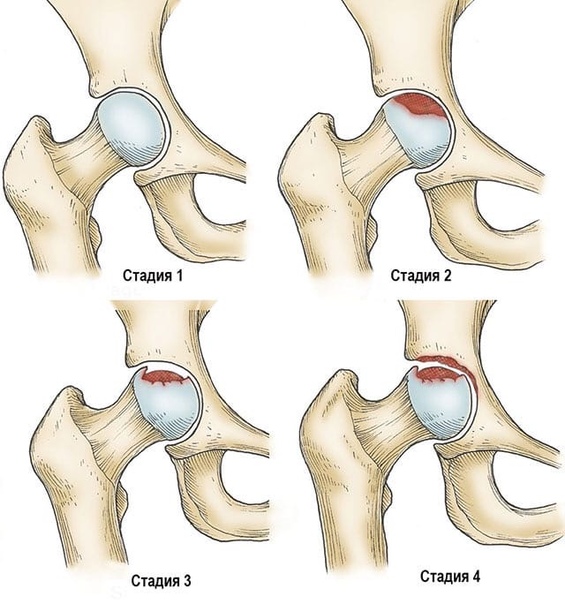

На рентгенограммах тазобедренный сустав сохраняет нормальную форму, суставная щель умеренно или неравномерно сужена с субхондральным склерозированием костных суставных поверхностей, непостоянными краевыми костными разрастаниями (I стадия).

Рентгенологически суставная щель может быть равномерно или неравномерно сужена, ацетабулярная суставная впадина уплощена, присутствуют явления субхондрального склероза, краевые костные разрастания. Конфигурация головки бедренной кости, как правило, не нарушена (II стадия).